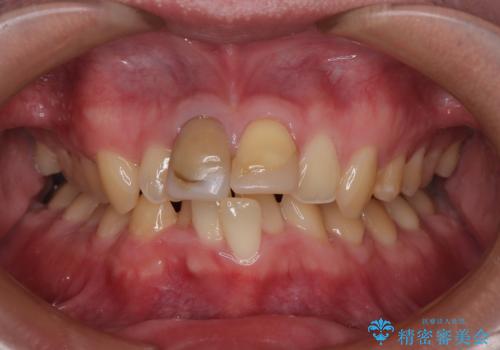

- 銀歯をセラミックにしたいとのことで来院された患者様です。

まず麻酔をして銀歯を外し、むし歯を除去し、形を整えて型取りします。

そして次の来院時、セラミックインレーを装着し、噛み合わせなどの調整を行います。

それを左右に分けて行いました。

インレーを装着するときは、唾液や血液による接着力の低下を避けるためにラバーダム防湿を行いました。

自然な色調で大変満足されました。